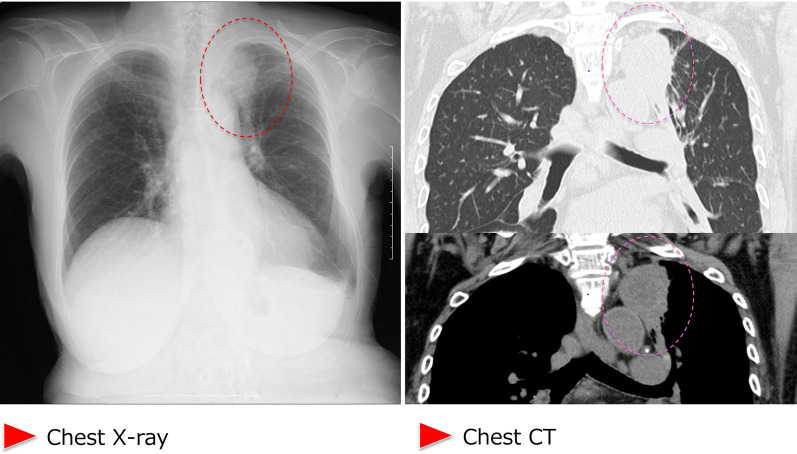

During supportive blood transfusion therapy, her condition was complicated by the following three infectious diseases: nontuberculous Mycobacterium (NTM) infection, pulmonary aspergillosis, and Escherichia coli bacteremia. The course of each of these diseases is summarized as follows. (1) NTM: In August 2020, she complained of hypoxemia (SpO2 level, 91%) and fever (37.5–37.9 °C). She visited the outpatient clinic at our hospital, and initial chest X-ray revealed multiple small granular shadows in both lungs (Fig. 2). She was positive for anti-MAC antibodies, and PCR was positive for Mycobacterium avium in the sputum. We thus diagnosed her with NTM infection. She received triple anti-Mycobacterium (azithromycin, rifampin, and ethambutol) treatment for 2 weeks. Consequently, the pulmonary granular shadows reduced, hematopoiesis recovered (with normalized platelet and erythrocyte counts), and precursor cell count in the peripheral blood decreased. This spontaneous remission status persisted for 3 months. Bone marrow examination was performed during the first spontaneous remission. Blast count was 4.6%, and chromosomal abnormality with del(5q) were detected in 2 of 20 analyzed cells (10%). Background myelodysplasia persisted, with hypogranular neutrophils, pseudo Pelger–Huet anomaly, megaloblastoid changes, ringed sideroblasts, and micromegakaryocytes. Flowcytometry detected a scanty of stem cell clones (1.8%) expressing abnormal phenotypes; HLA-DR+, CD13+, CD34+, CD117+, all of these are originally expressed aberrant phenotype. This result indicated that she achieved hematological remission with cytogenetically minor residual disease. (2) Pulmonary aspergillosis: In March 2021, she presented with fever (38.4 °C) and hypoxemia (SpO2 level, 93%) again. She was treated with levofloxacin for a few weeks, but it did not relieve her fever. In April 2021, chest X-ray revealed pneumonia, with a 43 mm-diameter nodule in her left upper lobe (Fig. 3). She showed elevated levels of β-d-glucan and Aspergillus antigen, suggesting pulmonary aspergillosis. She was treated with itraconazole followed by voriconazole for 20 days, after which inflammation and the lung nodule diminished. Following treatment, hematopoiesis recovered and blasts disappeared from the peripheral blood. The del(5q) clones in the bone marrow were detected in 2 of the 20 analyzed cells. She remained in the state of spontaneous remission for 5 months. (3) E. coli bacteremia: In December 2021, she presented to the outpatient clinic with a fever of 38.4 °C; she was positive for blood procalcitonin (1.55 ng/mL). We assumed that she had sepsis and thus hospitalized her on the same day. Upon hospitalization, ESBL-positive E. coli was detected in two sets of blood cultures, and meropenem treatment was provided. On day 10 of hospitalization, cellulitis of the right lower extremity developed with neutrophil recovery, and ESBL-positive E. coli was detected in the subcutaneous abscess at the same site (Fig. 4). The antimicrobial susceptibility to the isolated E. coli is shown in Fig. 4.

Fig. 3.

Chest X-ray and chest CT imaging of lungs with pulmonary aspergillosis. Images show a 43 mm nodular shadow in the upper lobe of the left lung. The dotted circle indicates the nodular shadow